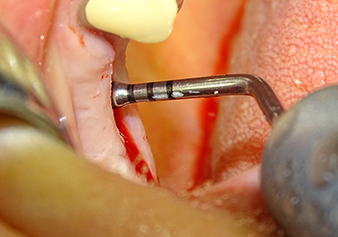

L’insert I2A (diamètre 2,0 mm) est ensuite utilisé pour perforer le plancher sinusien par intermittence et à la plus petite échelle possible. Cette méthode piézochirurgicale spéciale garantit que la membrane de Schneider n’est pas endommagée. Quand le Z25P est utilisé, la membrane est déjà légèrement relevée sous l’effet du fluide de refroidissement délivré via la pointe de l’insert (Fig. 3). Seulement 50 % du fluide de refroidissement sont éjectés afin d'éviter une pression élevée sur le site implantaire.